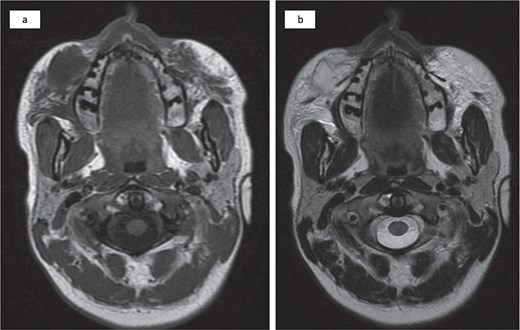

Magnetic resonance imaging revealed an injected cosmetic material in the subcutaneous tissue of the cheek on both sides, which was observed in the subcutaneous tissue of the cheek on both sides, with the right side showing a subcutaneous collection with an irregular wall and fat stranding with a low signal at T1 and a high signal at T2 (Fig. 2).

Bilateral injected cosmetic material observed in the subcutaneous tissue of the cheek with the right side showing a subcutaneous hypointense lesion at T1 (a) and a hyperintense lesion at T2 (b) with irregular borders, internal septation, and fat stranding.